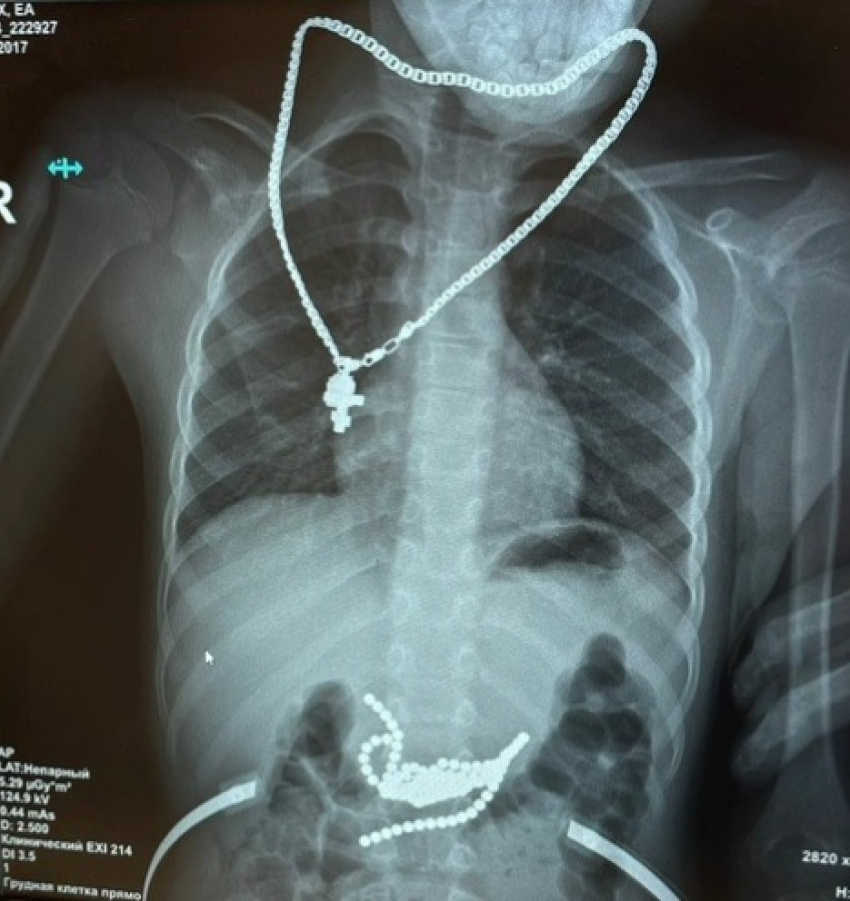

Хирурги Ростовской областной детской клинической больницы провели сложную операцию и спасли жизнь ребенку, который проглотил 50 магнитных шариков. Информация об этом появилась в социальных сетях лечебного учреждения.

Согласно сообщению, родители подарили мальчику магнитные шарики, чтобы помочь ему развивать мелкую моторику. Однако, вместо того чтобы использовать их по назначению, мальчик проглотил все шарики. При этом он не испытывал никаких болевых или дискомфортных ощущений, поэтому сообщил о случившемся родителям как бы между делом.

Несмотря на отсутствие явных симптомов, врачи приняли решение провести операцию, чтобы избежать возможных осложнений. Операция прошла успешно, и врачи смогли удалить все магнитные шарики. Теперь ребенок находится под наблюдением медиков и чувствует себя хорошо.